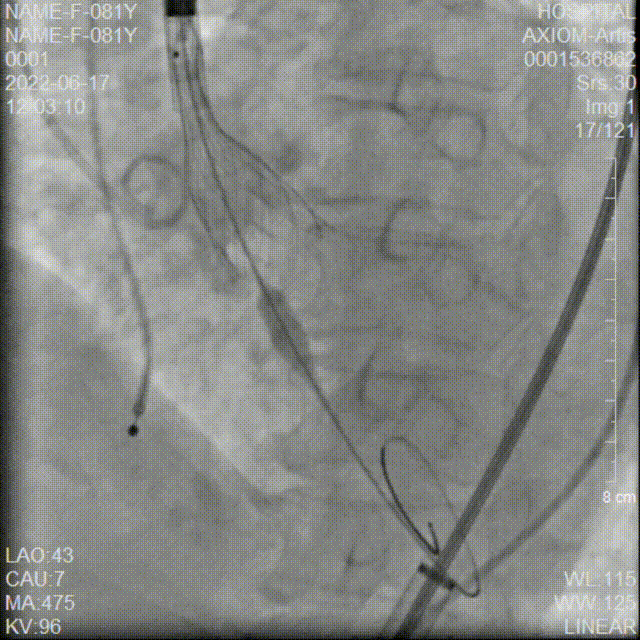

AV26瓣膜第二次释放到工作位

第二次释放到工作位造影检查

AV26瓣膜第三次释放到工作位

第三次释放到工作位造影检查

AV26瓣膜第四次释放到工作位

第四次释放到工作位造影检查

AV26瓣膜脱钩释放

AV26瓣膜完全释放后造影

20mm球囊后扩

后扩后造影

术中20mm球囊预扩可见明显腰征,没有瓣周漏,双侧冠脉灌注情况良好,随后选择AV26瓣膜。TaurusElite AV26瓣膜送至主动脉弓,输送系统轻松过弓及跨瓣。

本例手术为Type1型二叶式主动脉瓣重度狭窄合并中量返流的高龄心衰患者,重度钙化且分布不均匀,右冠窦内钙化向左室流出道衍生,左室流出道呈敞口形态,术中瓣膜释放过程中多次出现下滑,黎文生教授TAVR团队通力配合、全面细致评估,充分利用TaurusElite瓣膜系统优异的多次可回收功能,在瓣膜释放至工作位时多角度评估瓣膜植入深度、锚定力以及冠脉灌注情况,最后瓣膜释放定位位置接近瓣环。为使患者获益更佳,决定使用20mm球囊后扩改善瓣膜展开形态及组织贴合情况。

术后行主动脉根部造影检查与经食道超声影像评估,无瓣周漏,瓣膜形态良好,跨瓣压差由术前的107 mmHg即刻下降为0 mmHg,TaurusElite植入圆满成功!